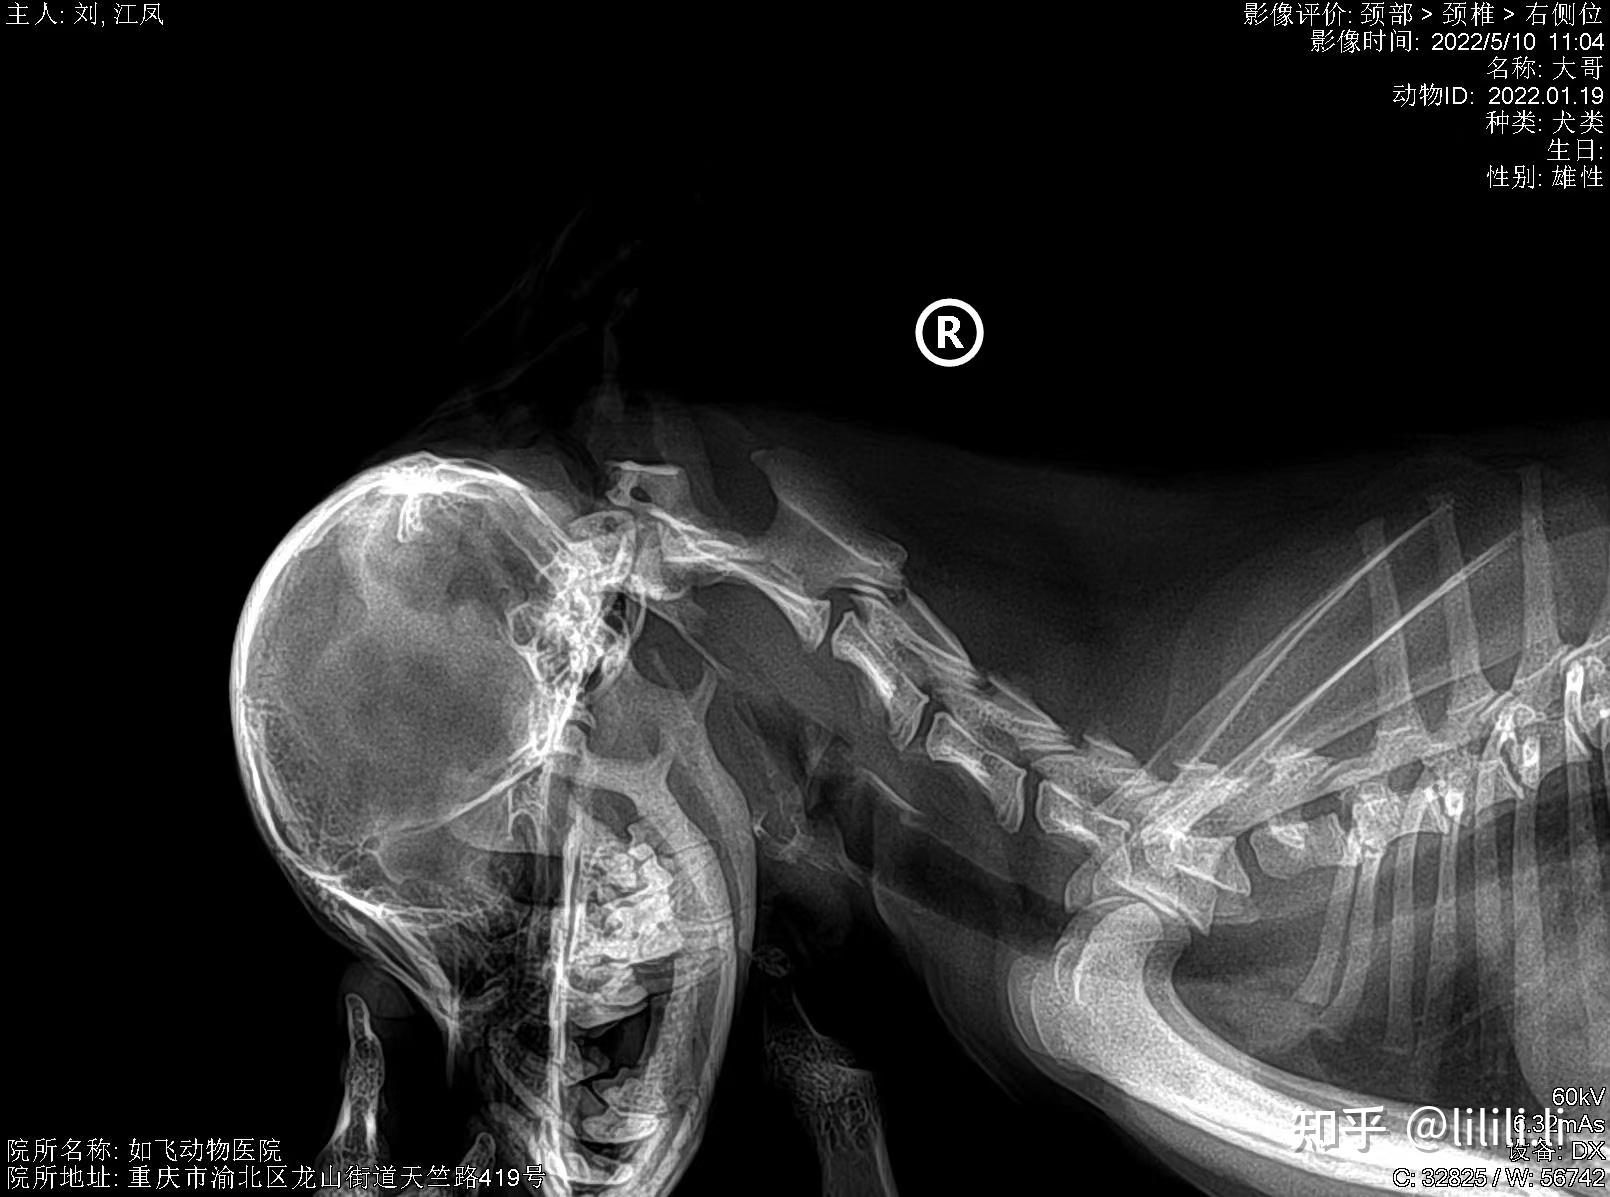

宠物dr拍摄诊断案例——寰枢椎半脱位

图片尺寸1610x1197